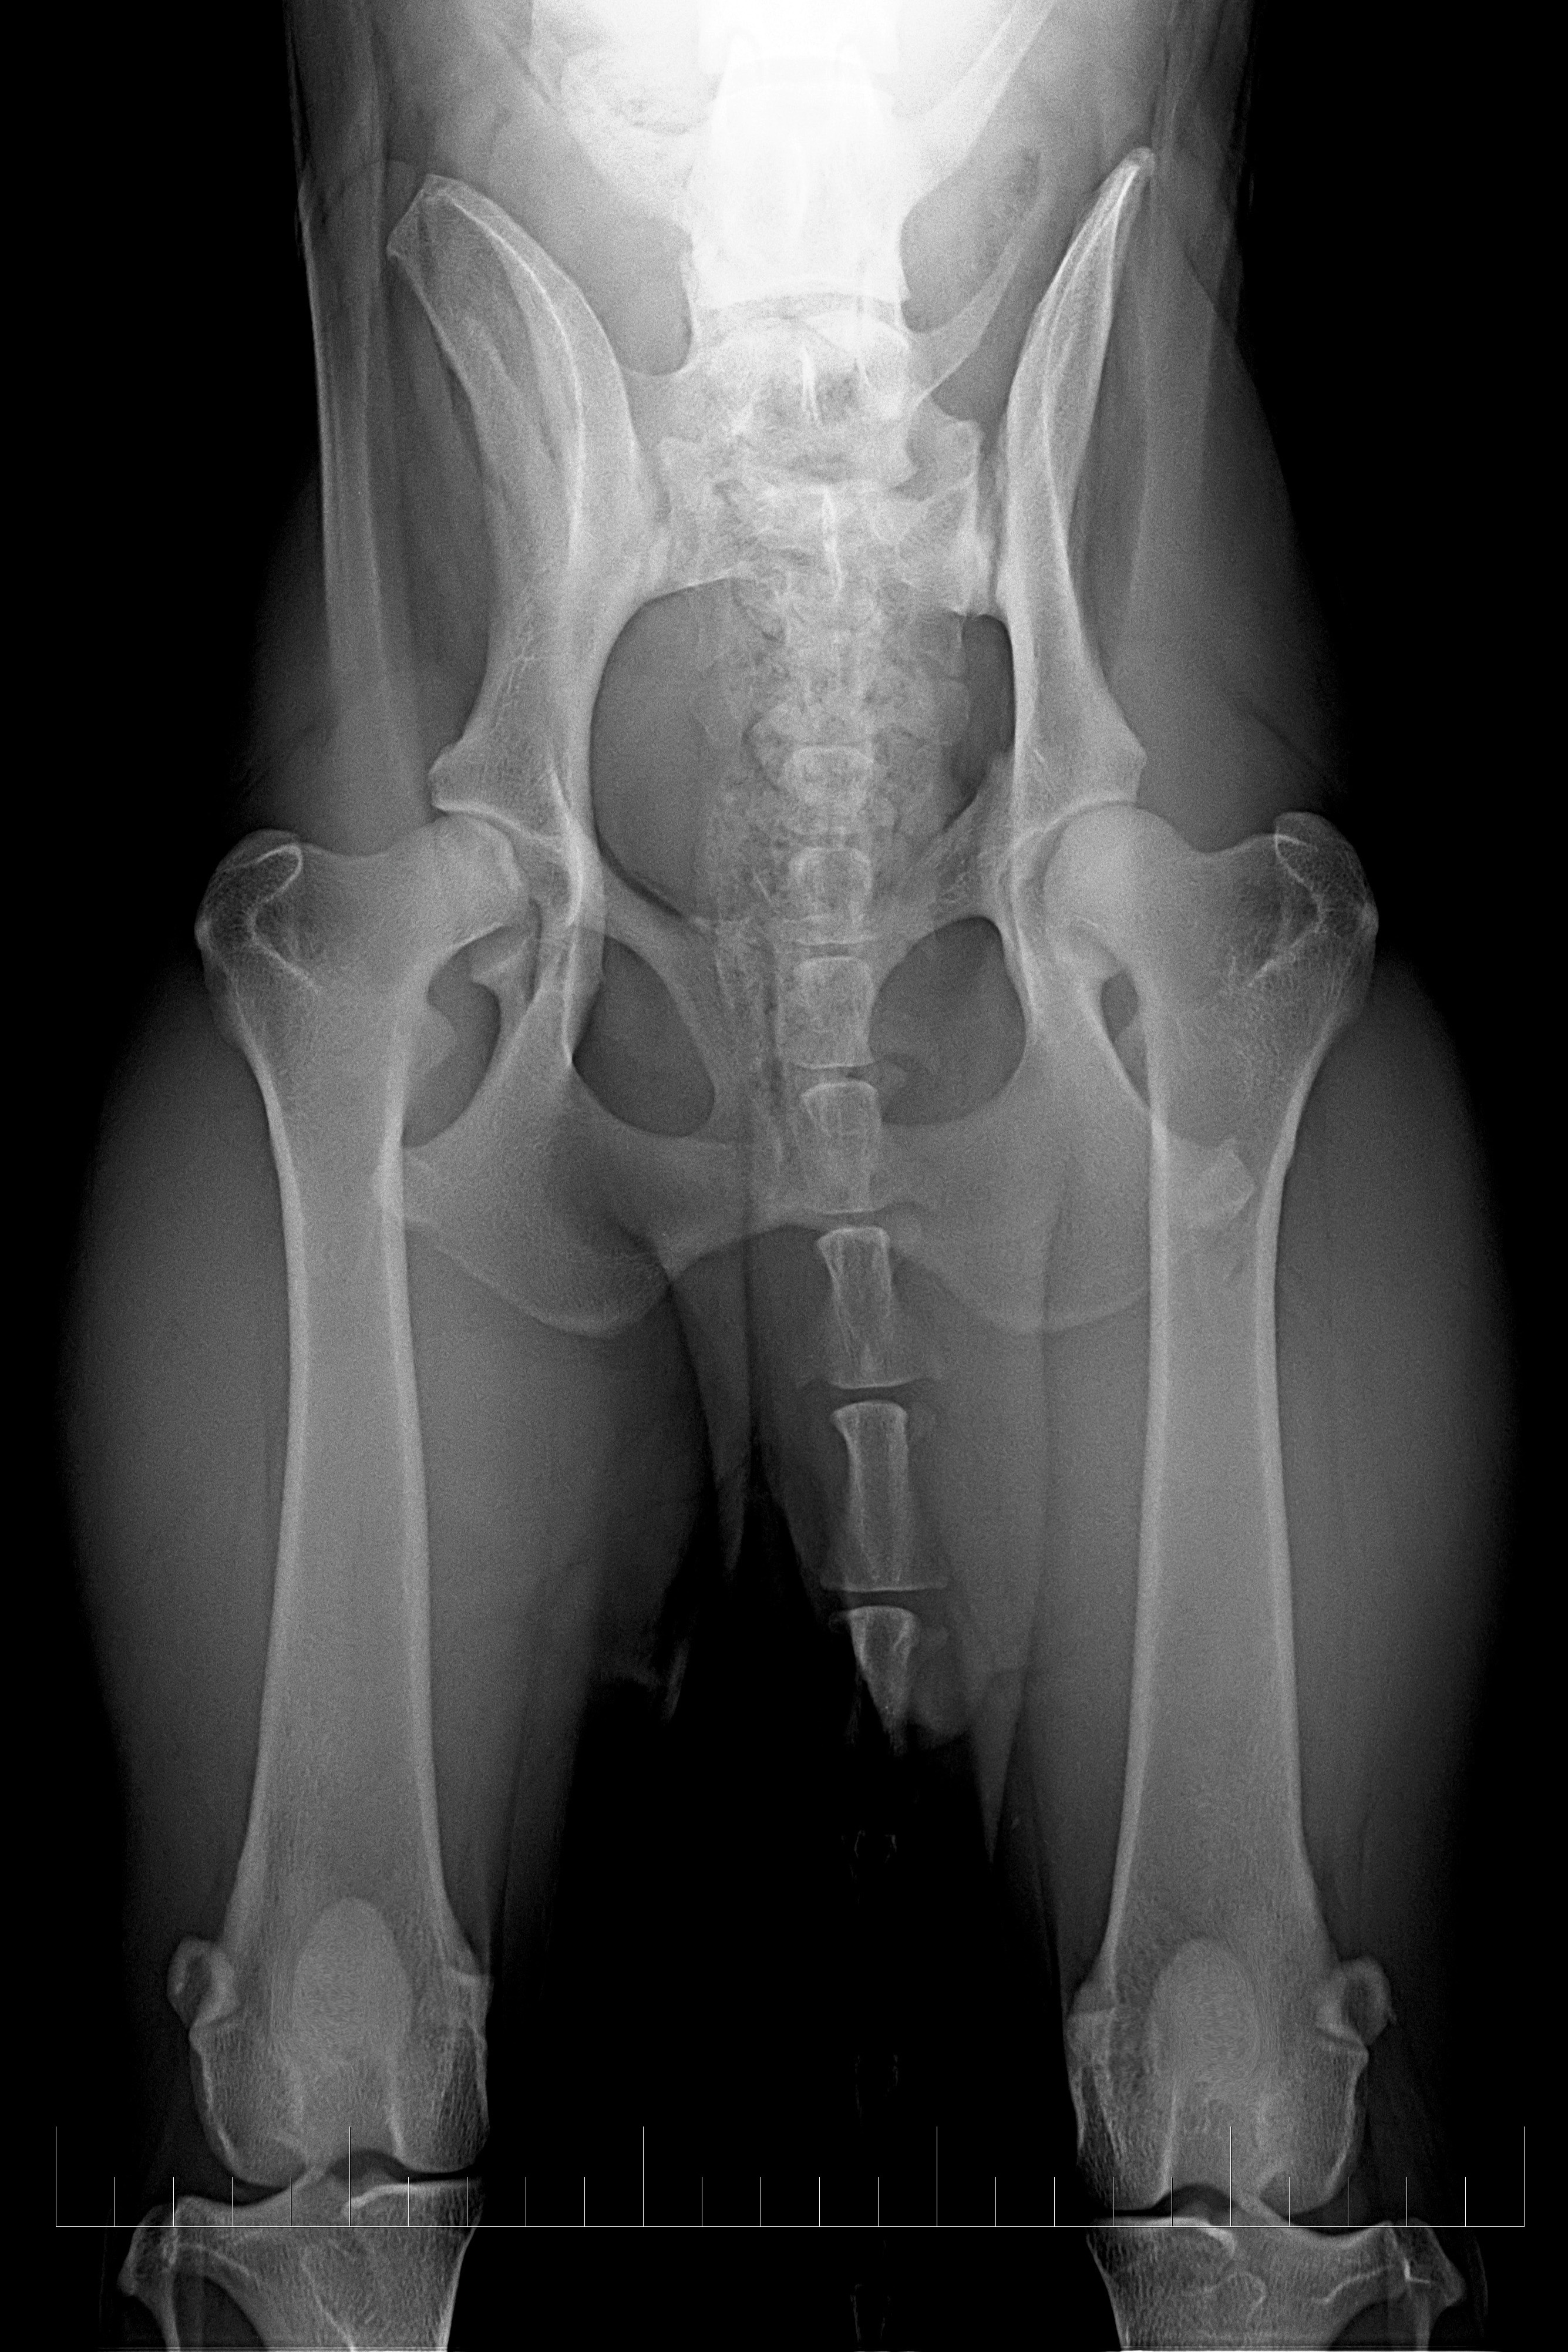

typ 3 u sedmiletého křížence